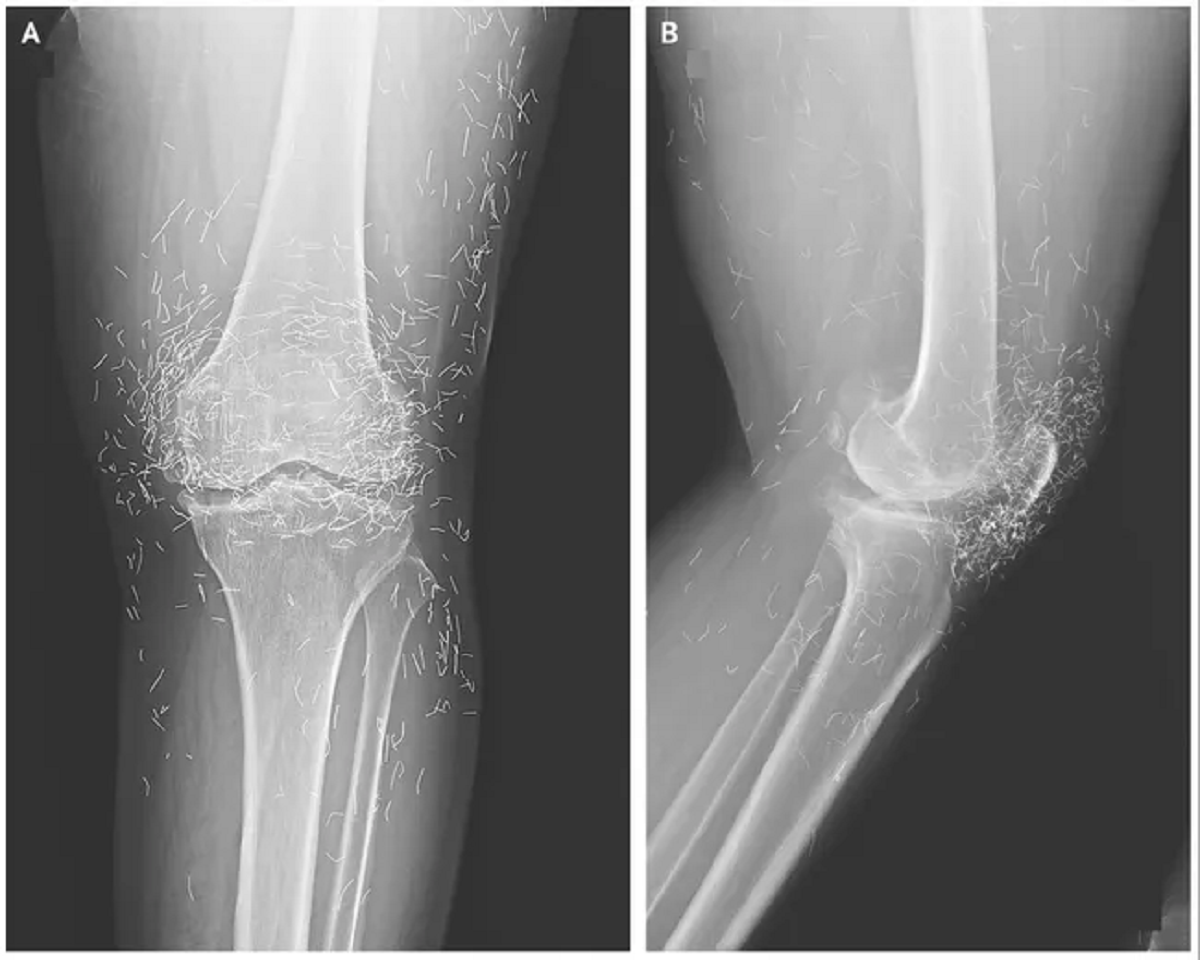

Στην συνέχεια αποφάσισε να πάει στο νοσοκομείο επειδή τα γόνατά της πονούσαν πολύ. Οι ακτινογραφίες του αριστερού της γόνατος αποκάλυψαν ότι το οστό της κνήμης στο εσωτερικό μέρος της άρθρωσης είχε παχύνει και σκληρύνει. Υπήρχαν επίσης οστικές αναπτύξεις, που ονομάζονται σπιρούνια, στα εσωτερικά τμήματα του οστού της κνήμης και του μηρού δίπλα στην άρθρωση του γόνατος.

Οι γιατροί είδαν επίσης εκατοντάδες στίγματα στην ακτινογραφία γύρω από την άρθρωση του γόνατος, τα οποία αποδείχθηκε ότι ήταν μικροσκοπικές χρυσές κλωστές. Στην συνέχεια ανακάλυψαν ότι οι κλωστές είχαν εισαχθεί στο πλαίσιο των θεραπειών βελονισμού της γυναίκας.

Αυτά τα μικρά, αποστειρωμένα χρυσά νήματα είχαν παραμείνει σκόπιμα στον ιστό για να παρέχουν συνεχή διέγερση. Οι γιατροί δεν ανέφεραν αν τα χρυσά νήματα αφαιρέθηκαν από τον ασθενή, αλλά σε προηγούμενες περιπτώσεις, τα νήματα έχουν παραμείνει στη θέση τους.

Στην έκθεσή τους για την περίπτωση του γόνατος, οι γιατροί σημείωσαν ότι τα χρυσά νήματα που εισάγονται κατά τη διάρκεια του βελονισμού μπορεί να καταστήσουν δύσκολη την ανάγνωση των ακτίνων Χ.